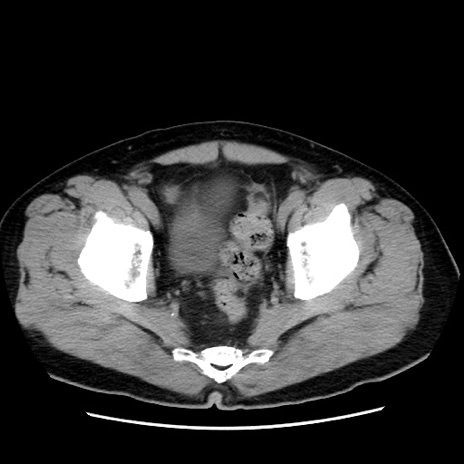

冠状断像

【症例】 70歳代男性

【主訴】 腹痛、嘔吐

【現病歴】 約1ヶ月前より間欠的に腹痛と嘔吐あり、当院消化器内科を受診したところCTで多発する肝臓のLDAを指摘され、精査中であった。以降は消化器症状は安定していたが、2日前より嘔気と腹痛があり、同日より排便・排ガスが消失した。改善認めず、 本日、救急外来を受診した。

【身体所見】意識清明・会話良好、BT 36.3℃、BP 127/80mmHg、 P 80bpm、腹部:膨満あり、平坦・軟、上腹部正中および下腹部正中に圧痛あり、反跳痛なし、筋性防御なし。

【データ】WBC 7200、CRP 0.77